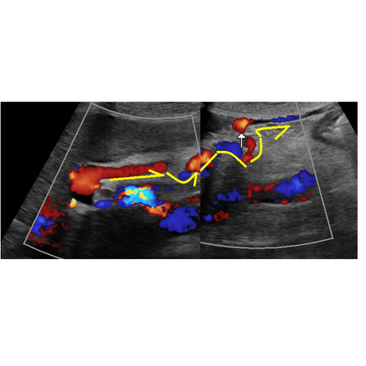

담낭 폐색을 의심, 급성무결석쓸개염의 확인, 음주력의 배경에서 간경화로 봐도 될 소견의 관찰 - 동대문구 답십리, 전농동, 우리안애 우리안愛 내과

60대 중반 남자, 초진 전농동 타의원에서 혈압/고혈압 투약중 어제 아침부터 배가 아프고 땡기고.. 지속중... 자다가 깨기도... 우상복부 민감한 압통의 확인, 다음의 경우와 같이 ... https://blog.naver.com/ejerci...